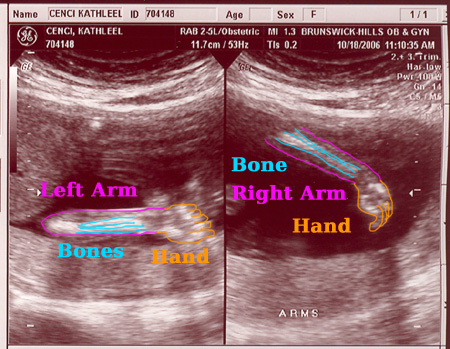

On October 18, 2006 we had the second sonogram. The baby is growing well. It was moving quite a bit while we were watching. It is amazing to actually see feet, arms, ribs, the spine, we even saw it sucking it's thumb. Check out the photos below. Each one is clickable which will bring you to labeled versions to help you identify what you're looking at. Enjoy!

Sonogram #2 - Image 5

Click on any/all of the photos above to see more. The links will give you full resolution photos and labeled versions. The labeling is my best guess as to what your looking at. We saw much more on the monitor, the motion version was awesome.